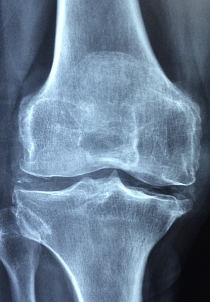

관절염은 연골이 손상되어 관절에 염증과 통증이 생기는 질환입니다. 콘드로이친은 연골 세포의 성장과 재생을 촉진하고, 연골을 분해하는 효소를 억제하여 관절염의 진행을 늦추고, 염증과 통증을 완화할 수 있습니다. 콘드로이친은 요통, 견통, 관절통, 근육통, 신경통 등 다양한 증상에 도움을 줍니다.

관절은 뼈와 뼈 사이에 있는 연골로 보호되고, 관절액으로 윤활되어 움직임이 부드럽고 유연합니다. 콘드로이친은 관절액의 점도를 높여주고, 수분 함량을 증가시켜 관절의 윤활작용을 강화합니다. 이는 관절의 마모와 충격을 방지하고, 움직임의 범위와 품질을 개선할 수 있습니다.